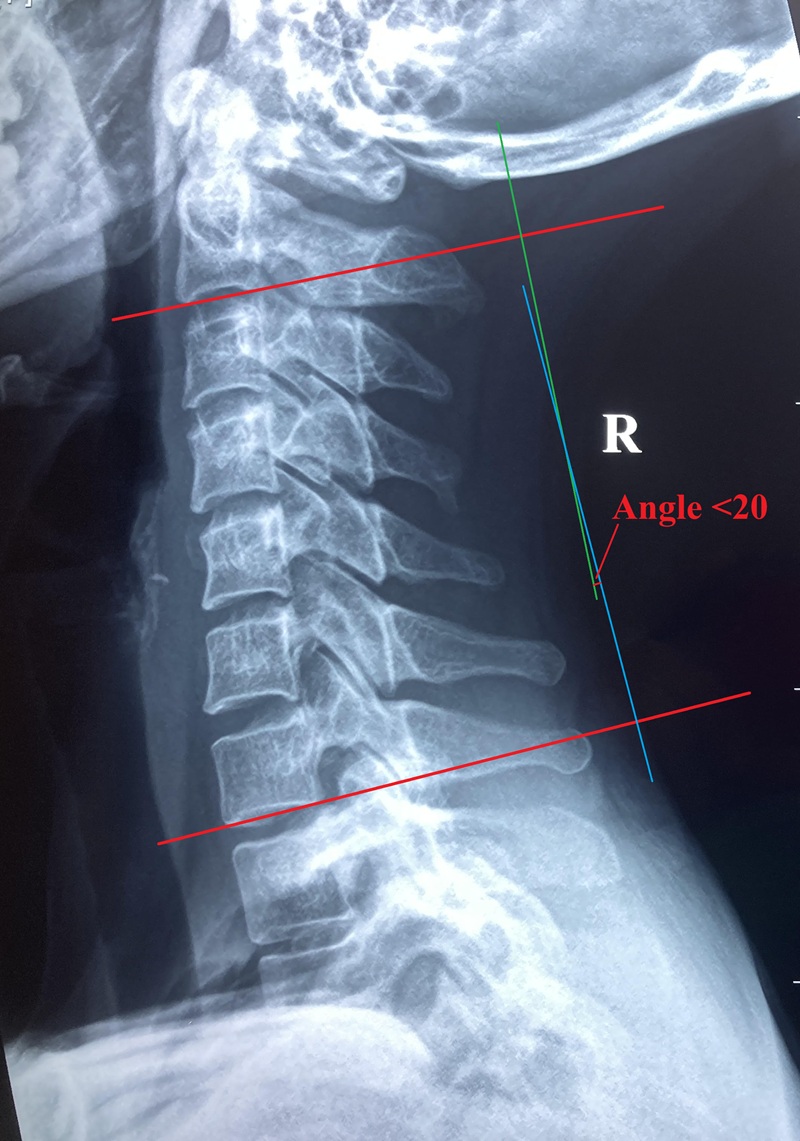

在功能方面,頸椎除支持頭部重量外,更負責協調頭部動作,配合頭部感官器官眼、耳、口、鼻感受環境變化及急機。致病原因如運動創傷或肌肉勞損都可以引起頸痛,寒背姿勢、工作壓力亦可促使頸痛發作。論病理發展,頸部肌肉、韌帶等軟組織傷患與頸椎關節疾患又可以互為因果引致痛症,嚴重者頸正常生理弧度拉直或反張。更甚者,長期頸痛往往伴隨抑郁等情緒病發作。

頸椎由七塊頸椎骨組成,範圍由髗底至背上端胸椎連接處:不典型頸椎(包括第一、二頸椎),典型頸椎(包括第三至七 頸椎),不同節段頸椎會共同參與頸運動,包括前屈後伸、左右傾斜及兩側旋轉的生理動作。頸椎骨有由上而下編排數目,例如頸一或簡稱C1;對於相連兩節頸椎標示,檢查報告會示 / 標記,例如C5/6 就代表頸椎骨第五及六之間處位置。明白數字標注會方便理解顯像報告所指位置。